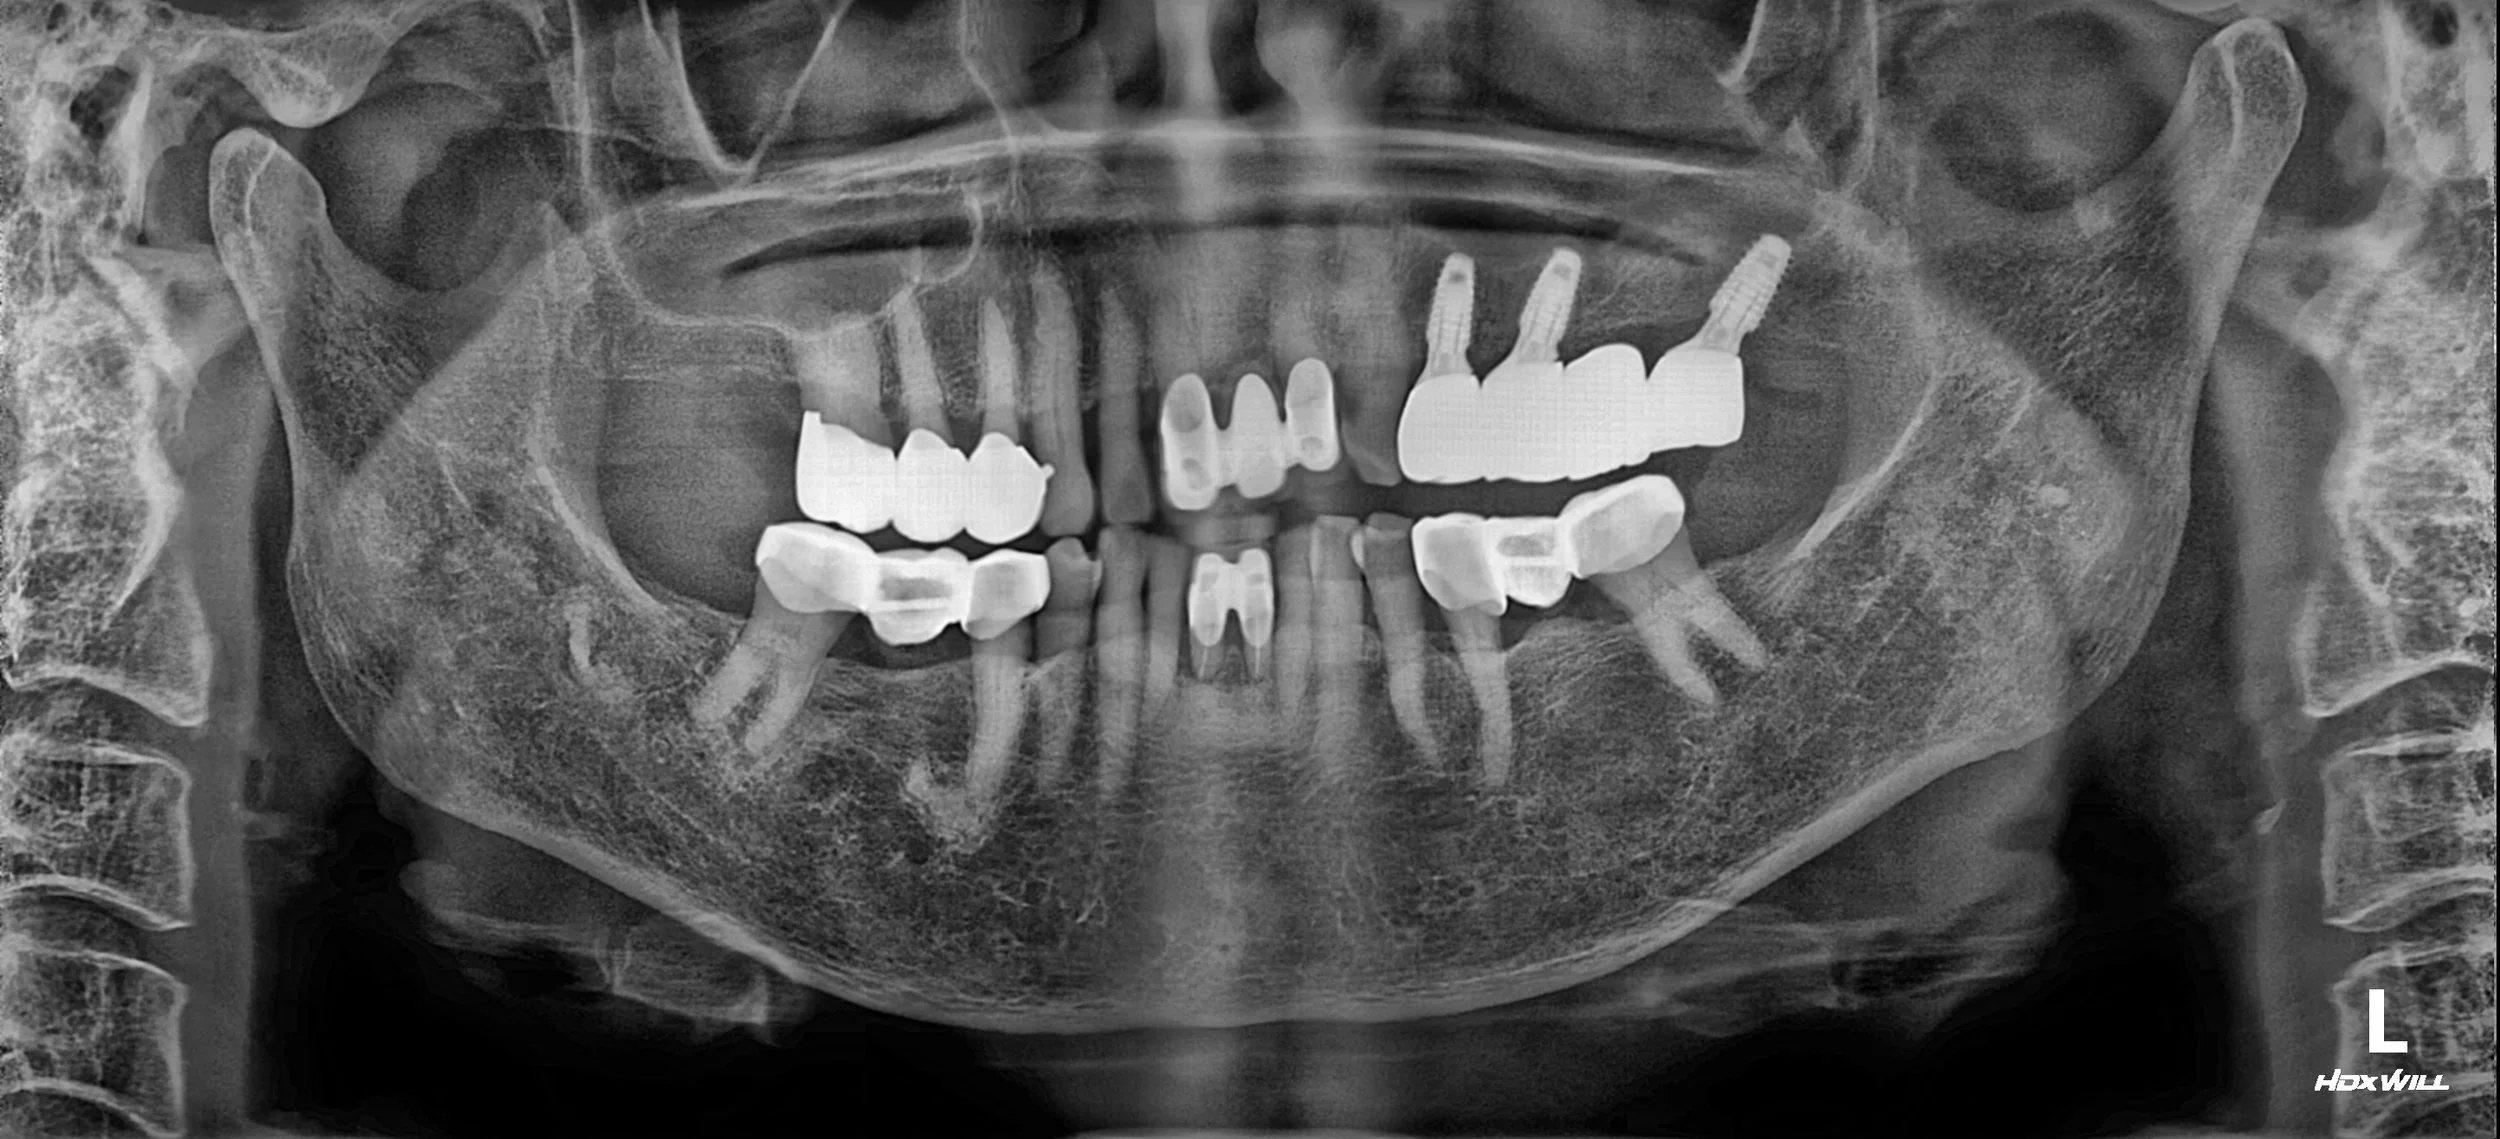

OPG - AFTER

A staged treatment approach was undertaken, beginning with the removal of the displaced implant fixture from the maxillary sinus and management of sinus pathology through guided bone regeneration (GBR).

Subsequently, implant placement and prosthetic rehabilitation were performed to re-establish both vertical and horizontal occlusal relationships, aiming for functional stability and long-term maintainability.

Digital diagnostic and planning tools were utilised to support precise execution and predictable prosthetic outcomes.